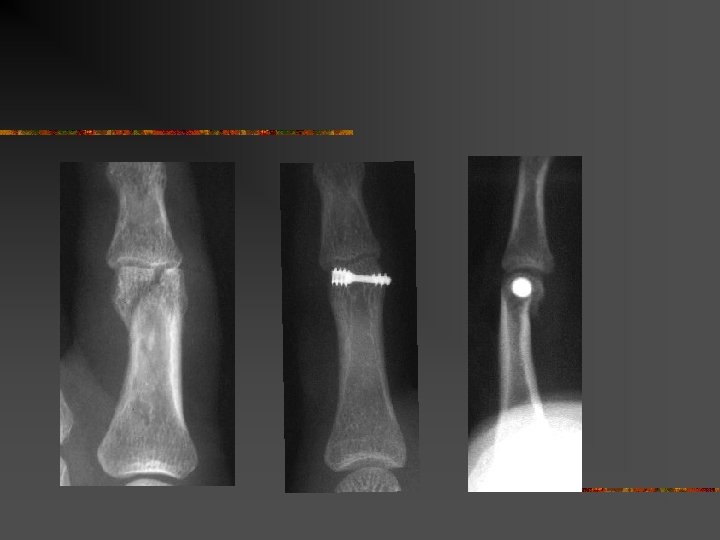

Indications : n Quelles fractures opérer ? Fractures instables ouvertes ou fermées (Fractures qui se déplacent spontanément après réduction) n Fractures articulaires n

Indications : n n Traitement chirurgical : Le but : n n Montage solide pour mobilisation précoce Eviter les raideurs

Méthode de traitement n n n Mobilisation immédiate = Tt fonctionnel Traitement orthopédique = immobilisation Traitement chirurgical = n n n Broches Vis et plaques Fixateur externe